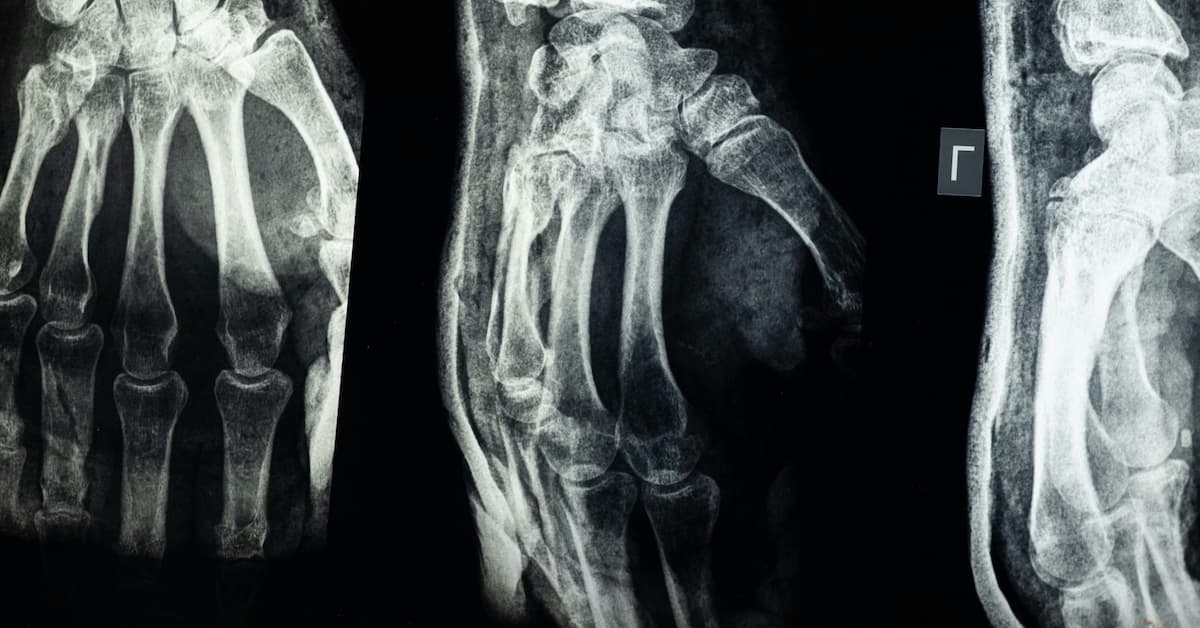

How Are Hand and Finger Fractures Diagnosed?

At Idaho Hand Center, diagnosis begins with a physical examination to assess swelling, alignment, and mobility. We often use X-rays to confirm the location and severity of the fracture. In complex cases, CT scans may be used for more detailed imaging.